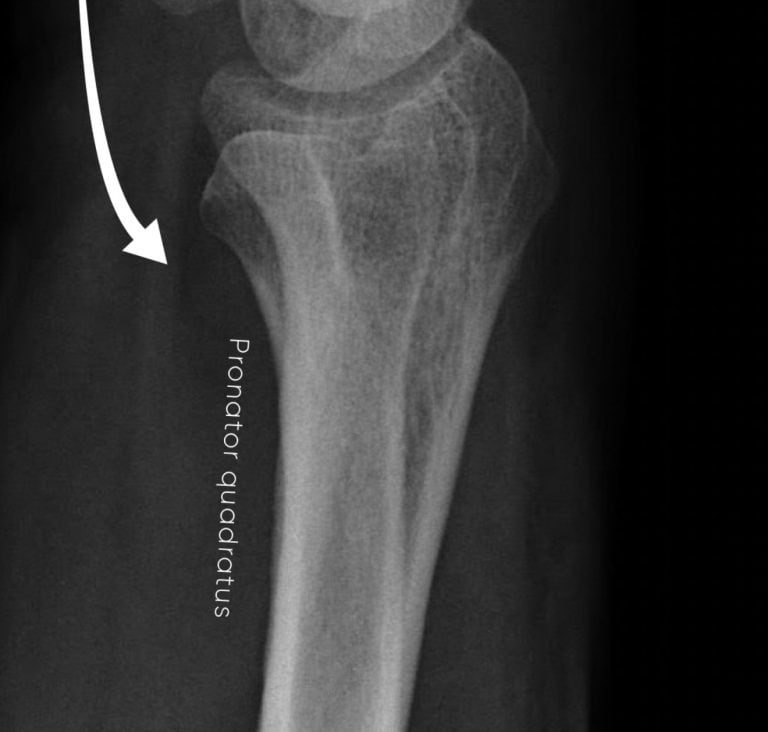

First, look at the soft tissues. Assess for general swelling and pay particular attention to the fat stripe on the palmar side of the distal radius. If this stripe is bowed or displaced, it suggests haematoma within the pronator quadratus muscle and should make you consider an underlying distal radius or ulna fracture. Note however this is a bit of a soft sign and if it isn’t there, it doesn’t mean there isn’t a fracture!

Check the fat stripe on the palmar side of the distal radius – it should be straight as it is here. Bowing or displacement could mean a fracture.